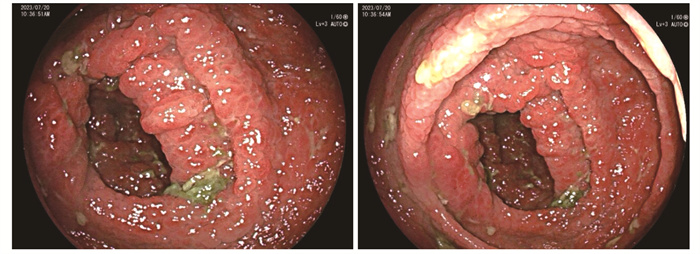

• 摘要: 本文报道Cronkhite-Canada综合征合并无症状新型冠状病毒感染1例。该患者临床表现为食欲减退,毛发及指甲脱落,皮肤色素沉着。内镜检查见胃、十二指肠及结肠黏膜呈弥漫性、大小不一、密集分布的息肉样改变。病程中检出新型冠状病毒核酸阳性。经中等剂量泼尼松治疗后,患者毛发恢复生长,皮肤色素沉着减退。本文总结该患者的诊疗经过并结合文献复习,以期提升临床医生对该病的认知。

Abstract: This article presents a case study of a patient who had Cronkhite-Canada syndrome in combination with an asymptomatic novel coronavirus infection. The patient exhibited clinical symptoms of loss of appetite, hair and nail loss, and skin pigmentation. Digestive endoscopy revealed widespread and varying-sized polypoid changes in the mucosa of the stomach, duodenum, and colon. During the course of the illness, the patient tested positive for novel coronavirus nucleic acid. Treatment with moderate doses of prednisone resulted in the patient's hair regrowth and decreased skin hypopigmentation. The article provides a summary of the patient's diagnosis and treatment and a review of relevant literature, with the aim of enhancing clinicians' understanding of the disease.